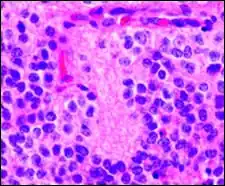

Perivascular pseudorosette

A perivascular pseudorosette consists of a spoke-wheel arrangement of cells with tapered cellular processes radiates around a wall of a centrally placed vessel. The modifier “pseudo” differentiates this pattern from the Homer Wright and Flexner-Wintersteiner rosettes, perhaps because the central structure is not actually formed by the tumor itself, but instead represents a native, non-neoplastic element. Also, some early investigators argued about the definition of a central lumen, choosing “pseudo” to indicate that the hub was not a true lumen but contained structures. Nevertheless, this pattern remains extremely diagnostically useful and the modifier unnecessarily leads to confusion. Perivascular pseudorosettes are encountered in most ependymomas regardless of grade or variant. As such, they are significantly more sensitive for the diagnosis of ependymomas than true ependymal rosettes. Unfortunately, perivascular pseudorosettes are also less specific in that they are also encountered in medulloblastomas, PNETs, central neurocytomas, and less often in glioblastomas, and a rare pediatric tumor, monomorphous pilomyxoid astrocytomas.[2]

Micrograph of perivascular pseudorosettes -